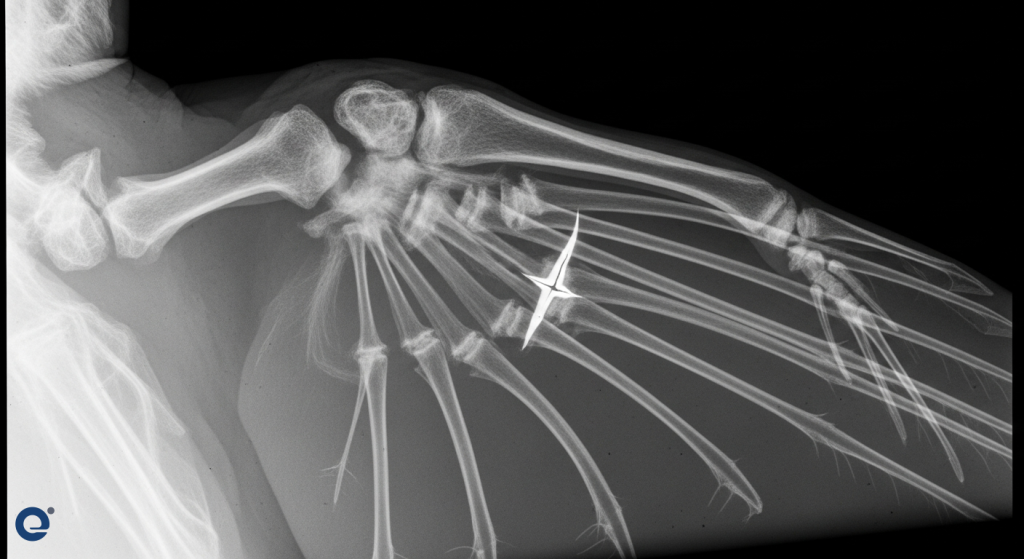

For example, a red-tailed hawk suffered a mid-shaft oblique fracture of its humerus. The veterinary team opted for surgery using a pin and wires. This approach is preferred for birds due to their lightweight bones. Plates and screws can be too heavy and may require removal later. The pin is easily removed without anesthesia after healing. The wires offer stability and are light enough not to impede flight.

Caring for exotic and wild animals presents unique challenges. Their delicate bone structure, physiological differences, and stress responses require specialized knowledge. For example, the choice between pins and wires versus plates and screws for birds highlights these species-specific considerations.